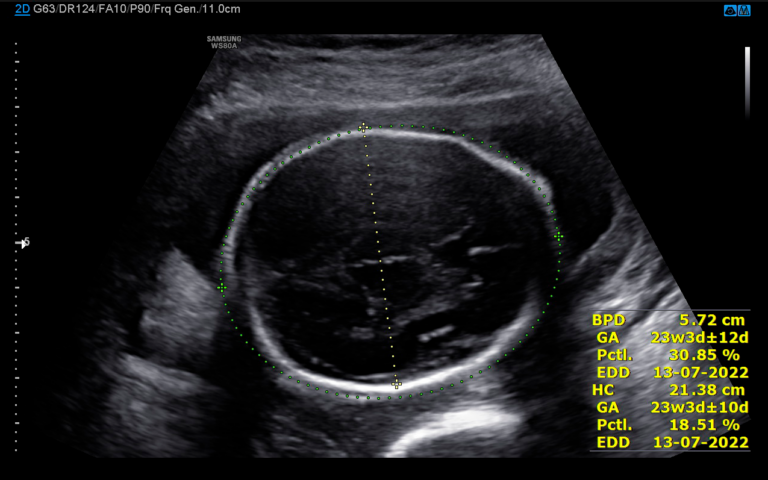

Idade gestacional pelo ultrassom é confiável?

Quando uma mulher descobre que está grávida, uma das primeiras coisas que ela quer saber é de quanto…